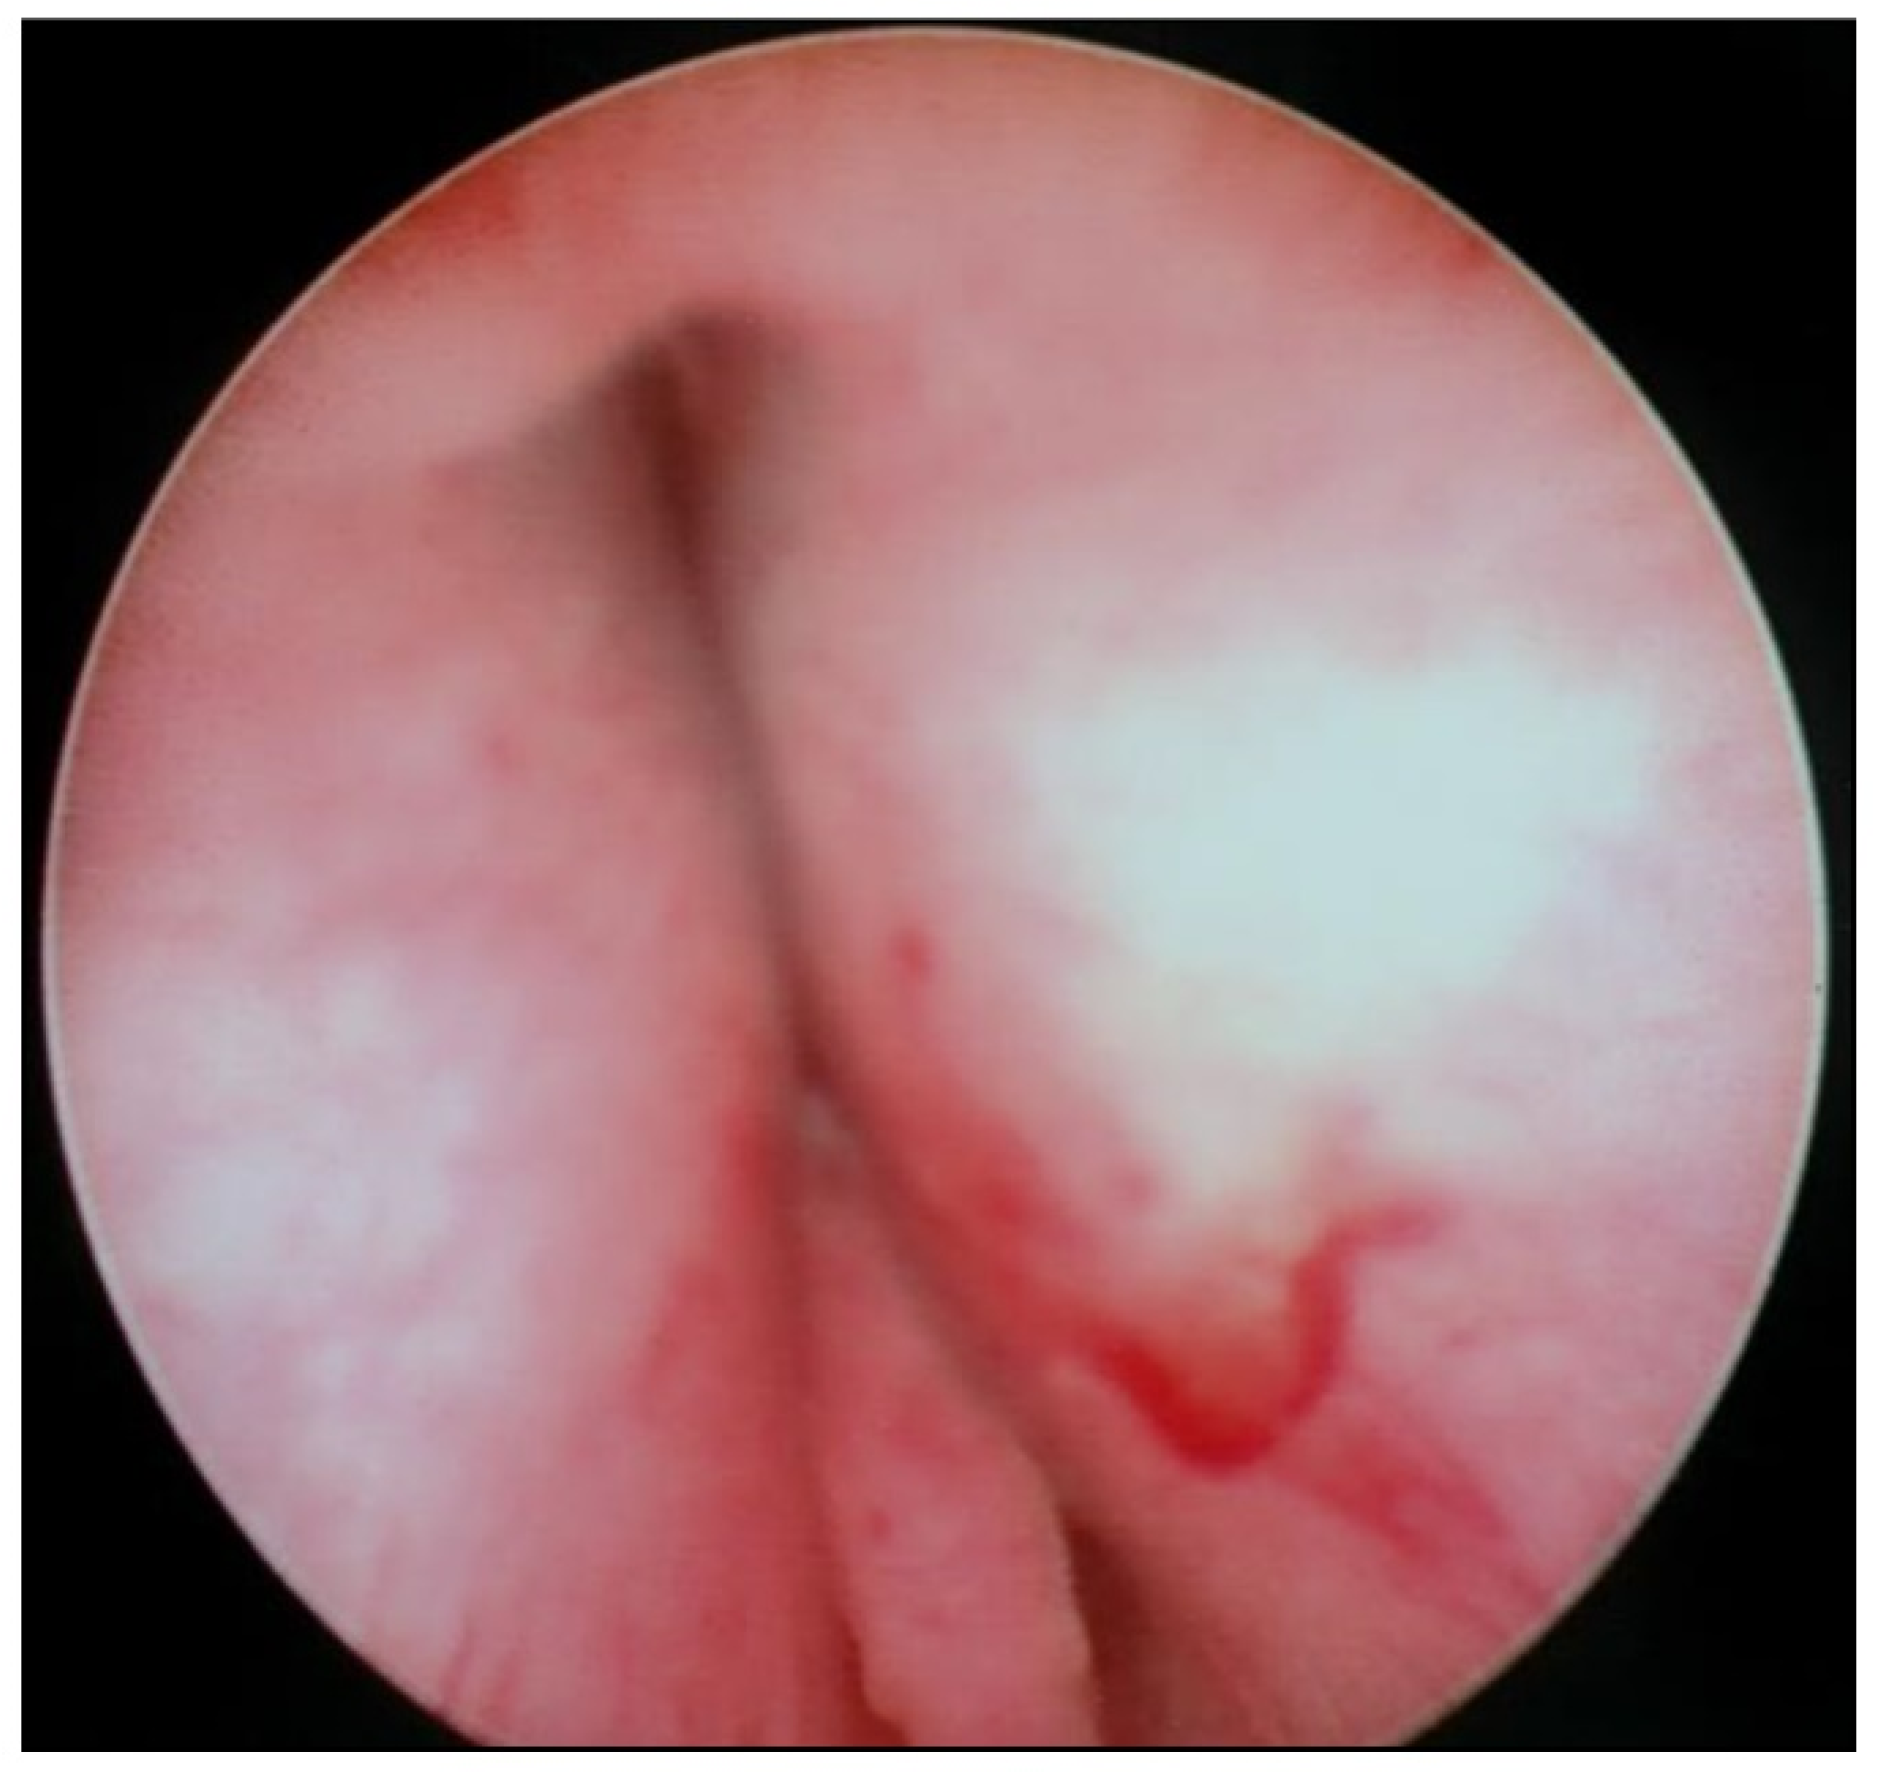

Transurethral cystoscopy displayed a wide open bladder neck at the beginning of the procedure (Figure 5). Under guidance by antegrade suprapubic endoscopy, transurethral retrograde bladder neck injection was performed at the 3 o’clock and 9 o’clock positions (Figure 6). Subsequently, bladder neck injection at the 6 o’clock and 12 o’clock positions was performed through antegrade percutaneous suprapubic endoscopy. Direct antegrade and retrograde visualization confirmed effectiveness of the luminal occlusion (Figure 7). As a (positive) consequence of effective injection, visibility of the optimal location for injection was compromised with increasing volume of the bulking agent. The combined injection technique is helpful to reduce this limitation as much as possible.

Figure 5.

Transurethral cystoscopy: wide open bladder neck.